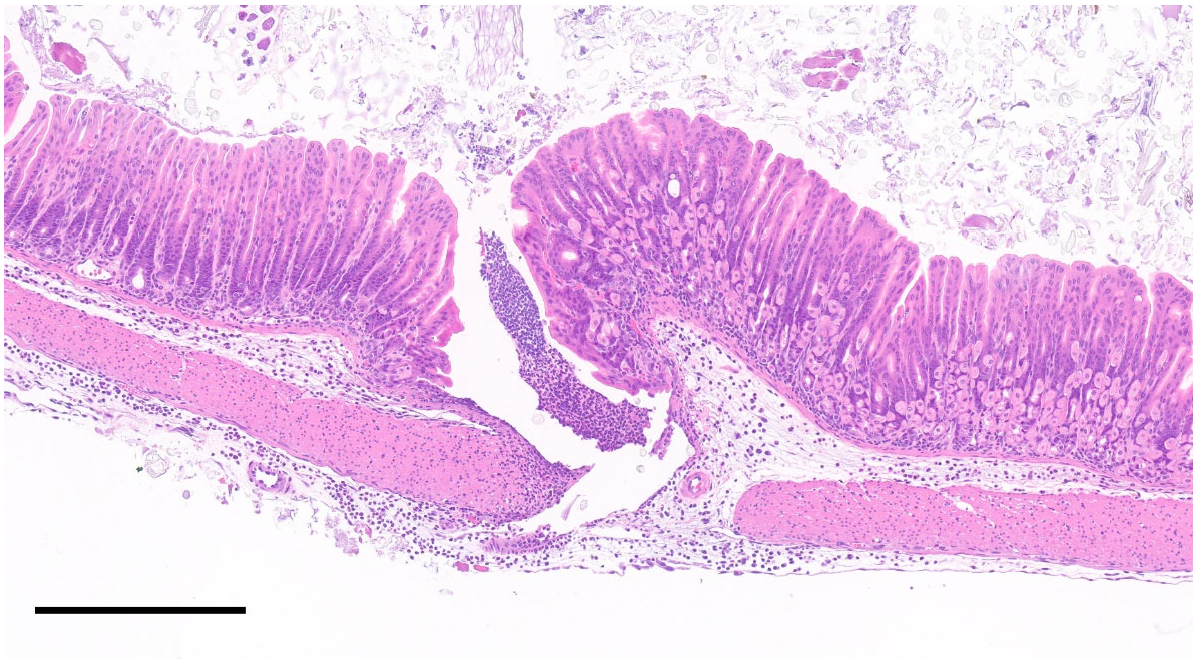

3.4. Peritoneal Injection-Related Findings